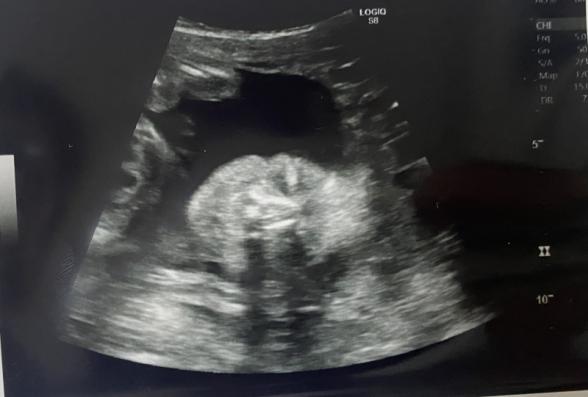

現在34週の妊婦です。今までもらったエコー写真を

整理して見返してたら胎児の鼻がちゃんと写ってなくて

鼻の骨がなかったり鼻が低いと生まれた時に異常があって産まれてくると聞いて心配になりました。

この写真から鼻に関して異常とか分かりますか?

赤ちゃんのお鼻がちゃんと写っていないということなのですが、お鼻の骨かなと思われるものは写っているように思いました。

異常になるのかどうかはわかりませんが、ちゃんとお鼻の骨はあるように思いました。

またかかりつけの先生にもご確認いただけたらと思います。